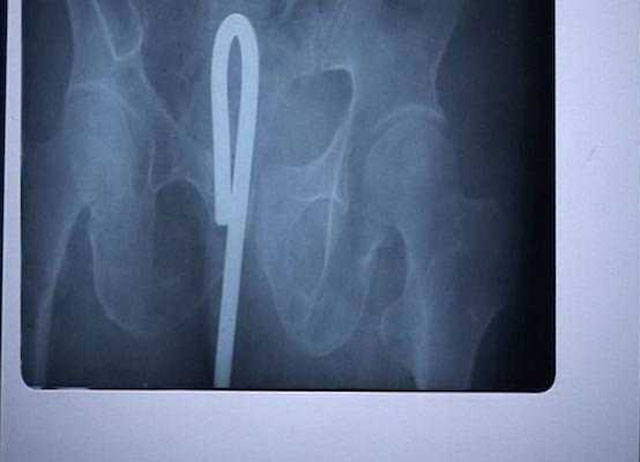

Man puts wire up his rectum to get stuck wine bottle.

Both get stuck. As ever.